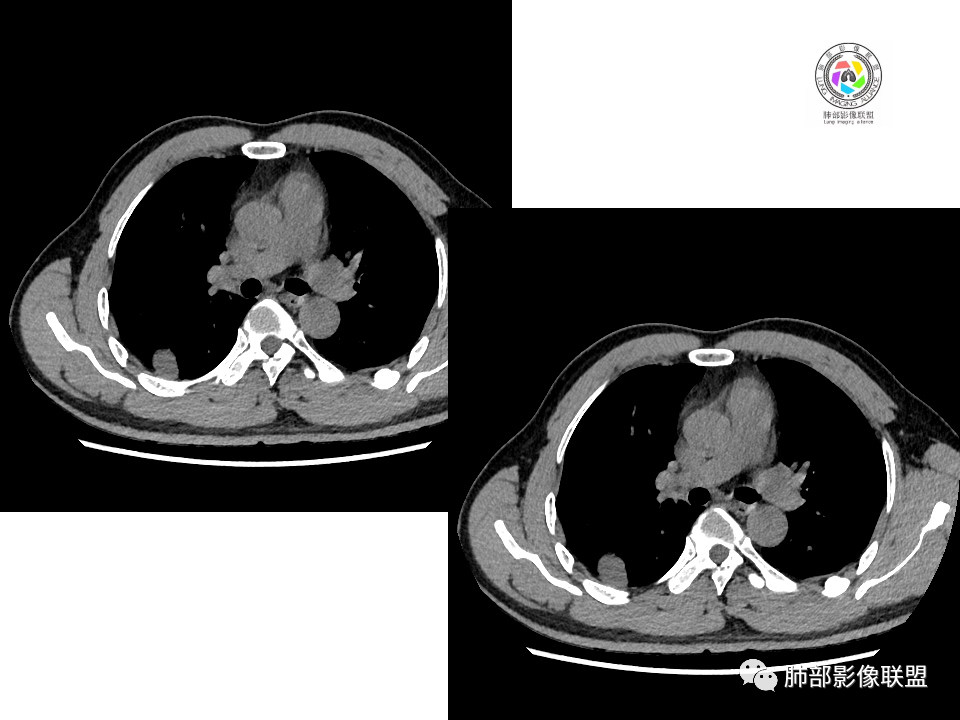

2.右肺下叶背段胸膜下块影,边界清楚光整,上下极见磨玻璃晕,未见明显分叶毛刺和棘状突起,未见胸膜凹陷或胸壁侵入。密度均匀,轻度不均匀强化。未见支气管进入。

3.右肺中叶外侧段胸膜下散在小片影,磨玻璃密度为主,边界不清,支气管相关。符合炎性特征!

4.右肺下叶基底段支气管血管束旁小结节影,边界清楚,强化不明显。注意,这结节在“遥远的”基底段。

显然本例焦点在于背段那个边缘光整的块影!

1.边缘光整干净,大病灶缺乏坏死等,不符合鳞癌影像学特征。尽管有吸烟史,还是偏年轻。

2.边缘光整,会是小细胞癌或是大细胞癌吗?小细胞癌的肺门纵隔淋巴结增大往往十分夸张,该患者不符合。

注意,基底段支气管血管束旁的小结节影,即便是淋巴结,也与背段病灶引流途径不符。